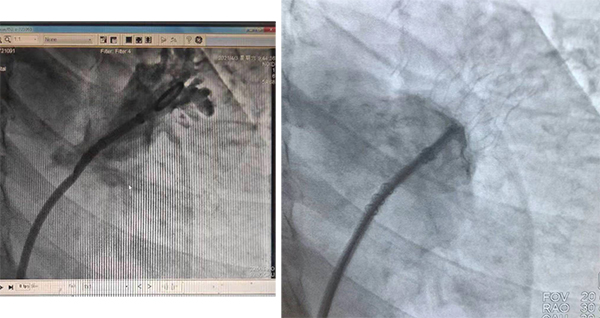

封堵傘術(shù)前、后影像對(duì)比

在介入導(dǎo)管室、麻醉科等多學(xué)科的配合幫助下,王又平主任通過微創(chuàng)的方法,將傘形MemoLefort封堵器發(fā)放至患者左心耳根部,成功為患者完成經(jīng)導(dǎo)管左心耳封堵術(shù),術(shù)后患者無不適,復(fù)查超聲左心耳完全封堵,無分流現(xiàn)象。